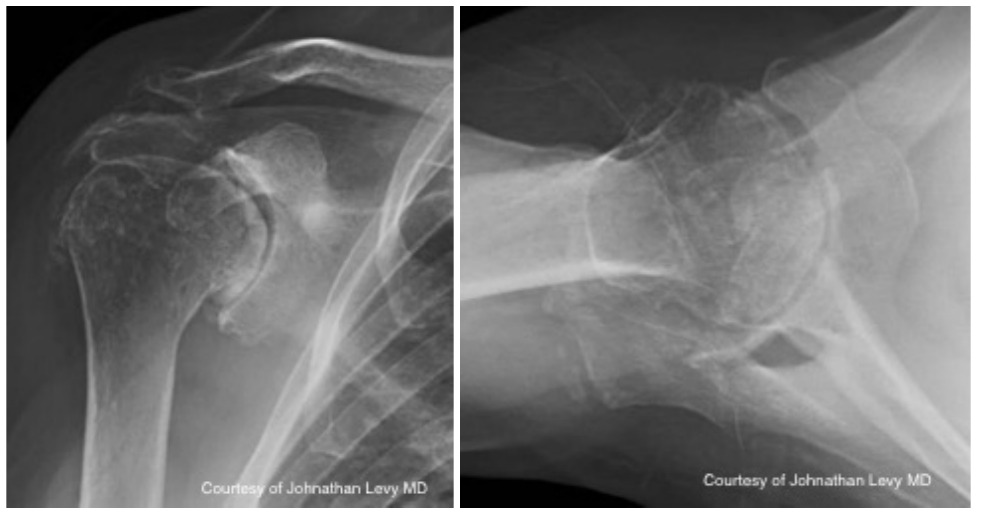

Case two is an 86-year-old female with long standing left shoulder pain and loss of function. Preoperative exam shows 70° of active forward flexion, neutral external rotation, and internal rotation to the lateral thigh. Radiographs (Figure 5) and CT scan (Figure 6) show significant posterior bone loss and retroversion with medialization of the joint line. Options include asymmetric reaming, an augmented component, or bone grafting. An augmented reverse baseplate was selected for this elderly female. Radiographs at six months show a well fixated baseplate with improvement of the pre-operative retroversion (Figure 7).